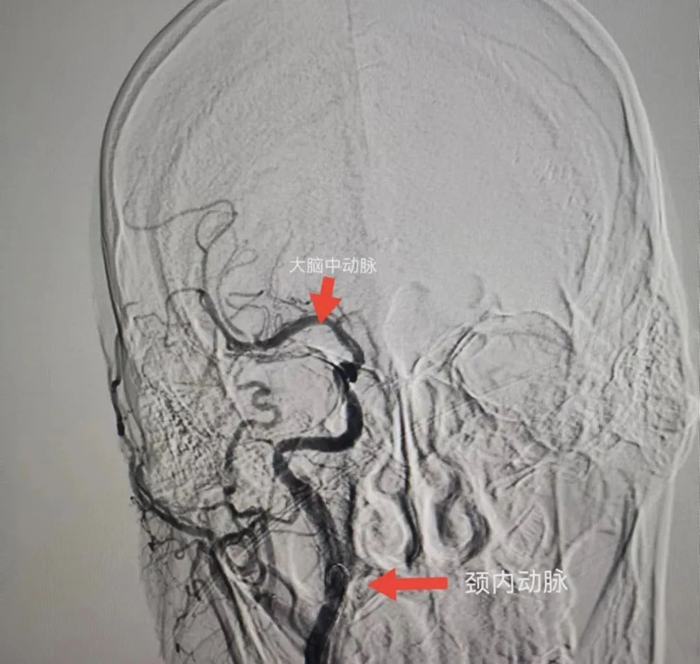

與患者女兒溝通,征得患者女兒同意后,立刻聯(lián)系CT室,半小時內(nèi)完成CT檢查,證實患者右側(cè)頸內(nèi)動脈和右側(cè)大腦中動脈閉塞,存在70毫升的缺血腦組織,有取栓適應(yīng)癥。再次和患者女兒溝通,患者女兒接受風(fēng)險簽字手術(shù)。立刻聯(lián)系介入室和麻醉科,一個半小時完成手術(shù)。

術(shù)中給予患者右側(cè)頸內(nèi)動脈植入支架和右側(cè)大腦中動脈取栓,患者血管達(dá)到3級再通。術(shù)后第二天,患者神志轉(zhuǎn)清醒,左下肢可抬起。術(shù)后第5天,患者左側(cè)肢體均可活動達(dá)到4級肌力,左手可持物,能獨立行走。

患者腦CTA結(jié)果

血管內(nèi)治療后的結(jié)果